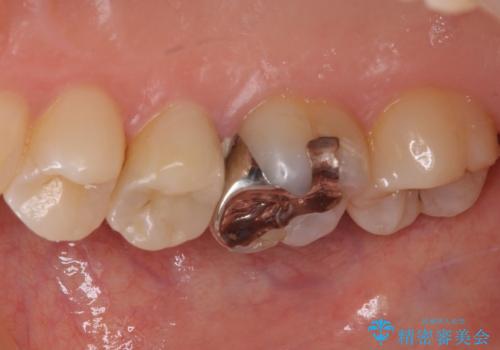

- 冷たいものがしみるとのことで来院された患者様です。

レントゲン写真より、第一小臼歯にやや大きい虫歯があることが分かりました。

症状などから診断したところ、神経を取る可能性は低いと考えられたため、セラミックインレーによる修復治療を行うこととしました。

奥の大臼歯にもむし歯があったので、一緒に処置を行いました。